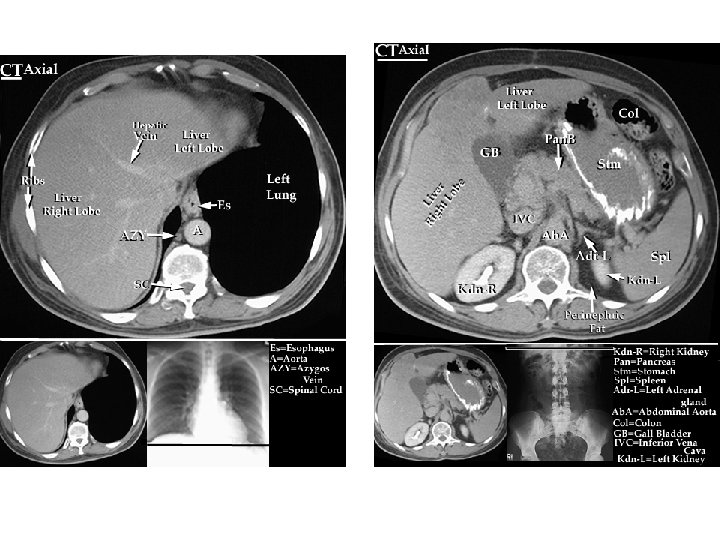

Undersøkelsesmetoder, operative metoder l Undersøkelsesmetoder: – – l Ultralyd Røntgen, røntgen m. kontrast CT, MR Endoskopier: Gastroskopi, rectoskopi, colonoskopi, ERCP evt. med papillotomi og steinekstraksjon. Operative metoder – – Laparoskopiske metoder Åpen kirurgi